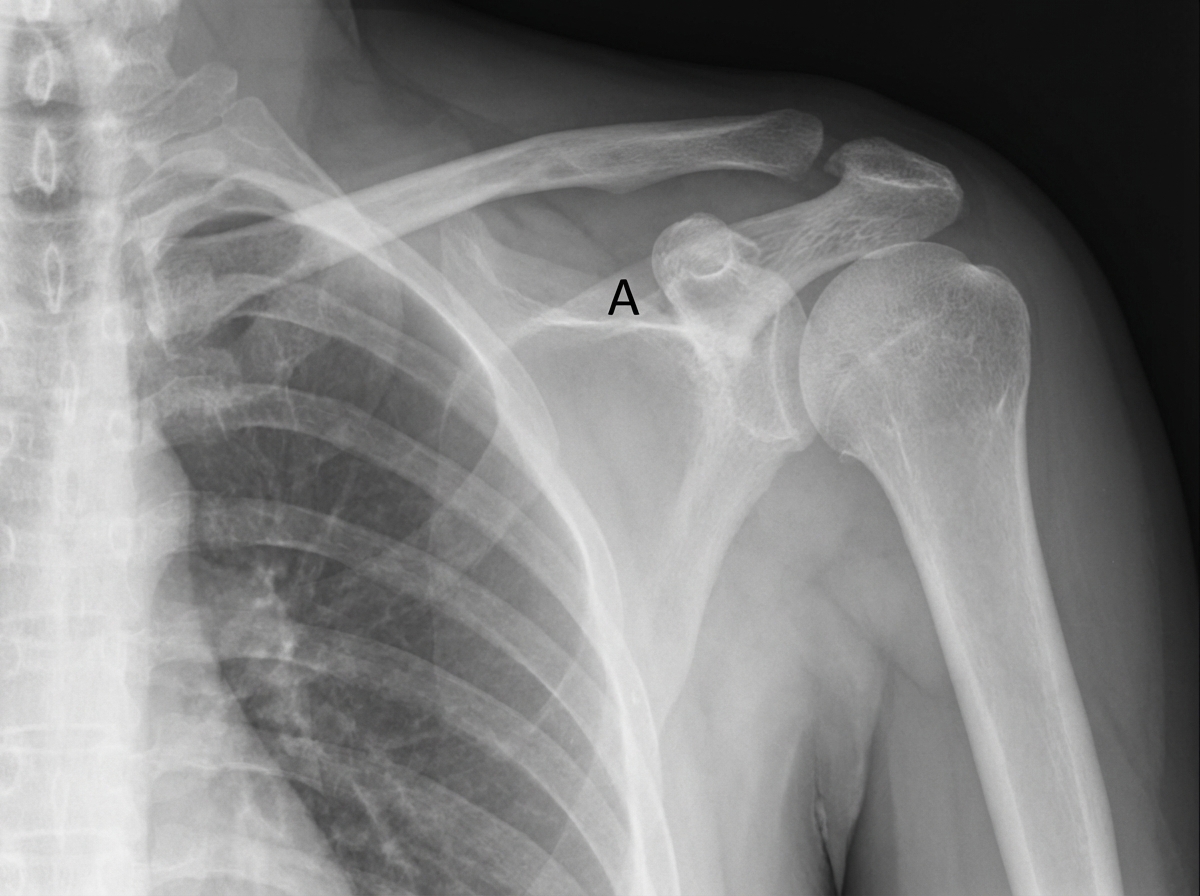

An 11-year-old boy falls down the stairs. A physician examines a radiograph of the boy's shoulder region. If the structure indicated by the letter A is calcified, which of the following muscles is most likely paralyzed?

Explanation: ***Infraspinatus*** - Structure A represents the **suprascapular ligament** at the **suprascapular notch**, and its calcification compresses the **suprascapular nerve**. - The **suprascapular nerve** specifically innervates the **infraspinatus muscle** (along with supraspinatus), making it the only option affected by this compression. *Deltoid* - Innervated by the **axillary nerve** (C5-C6), which passes through the **quadrangular space** below the shoulder joint. - Calcification of the **suprascapular ligament** does not affect the **axillary nerve** pathway or the deltoid muscle function. *Teres major* - Supplied by the **lower subscapular nerve** (C6-C7), a branch of the **posterior cord** of the brachial plexus. - The **suprascapular nerve** compression has no impact on the **subscapular nerves** or teres major function. *Teres minor* - Innervated by the **axillary nerve** (C5-C6), similar to the deltoid muscle. - Calcification at the **suprascapular notch** does not involve the **quadrangular space** where the axillary nerve travels.